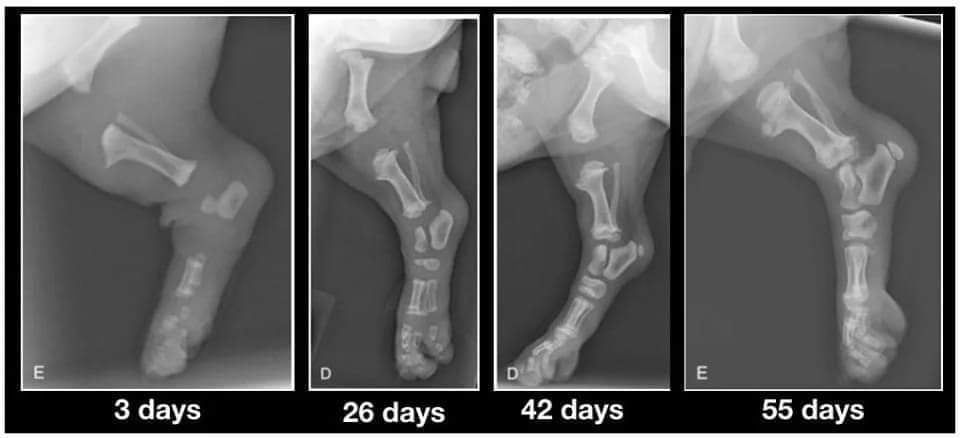

Photos Veteriankey.com @ 62 jours

L'ossification endochondrale (le processus durant lequel le cartilage se transforme en os), diffère selon la taille adulte du chiot. L’ossification complète avec fermeture des plaques de croissance se produit entre 3 mois dans les races de mini et 24 mois dans les grandes races (voir photos) ...

Un exercice excessif et une nutrition inadéquate pendant ces périodes peuvent conduire à des problèmes de conformation et à la malformation des os, ce qui peut entraîner arthrose, maladie articulaire dégénérative et autres troubles musculo squelettiques.